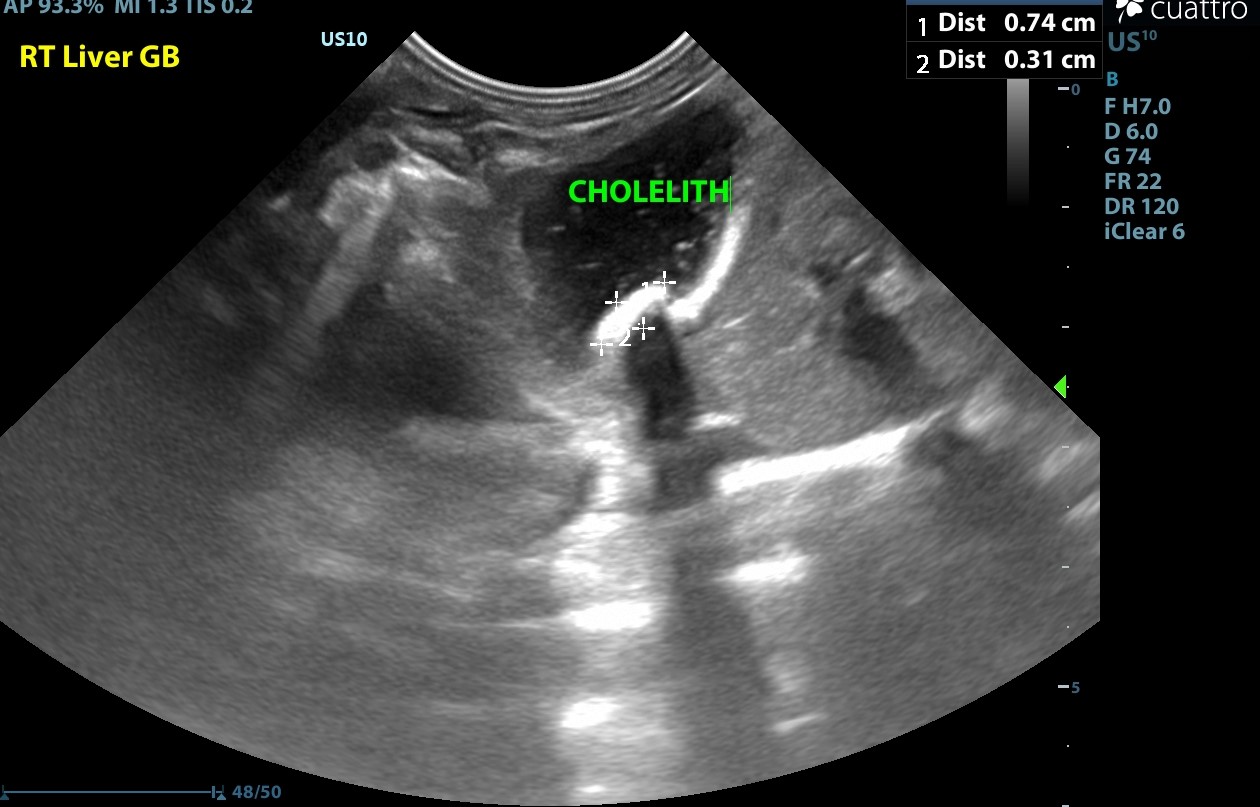

Normal size, shape and echogenicity. No focal lesions are appreciated. The gall bladder is moderately distended with normal anechoic and hyperechoic suspended hyperechoic foci and a dependent ovoid mineralization which casts a strong distal acoustic shadow measuring approximately 0.7 x 0.3 cm that is not resulting in obstruction. No common bile duct dilation is seen.

Cholelithiasis the finding is mild - DDx: Neoplasia (gall bladder, common bile duct), cholangiohepatitis, hepatitis, hypercholesterolemia, hyperbilirubinemia, hypertriglyceridemia, dietary, gallbladder dysmotility

Image of organized, dependently-oriented mineralization in the gallbladder which is not obstructive. The mineralization creates a void distal to the projected ultrasound waves in a characteristic linear shape.